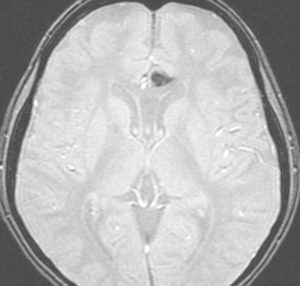

放射線誘発膠芽腫(グリオブラストーマ)

松果体のジャーミノーマのために,19歳の時に全脳照射30グレイと松果体局所照射20グレイを受けました。これは28歳の時に発生した右側頭葉の膠芽腫です。この部分には30グレイしか入っていないのですが,2.5グレイという大きな1日線量が用いられていました。またslit-beam rotationという1990年代初頭に用いられた照射方がされています。同じ線量であっても二次ガンを招きやすい照射法というのがあるのかもしれません。